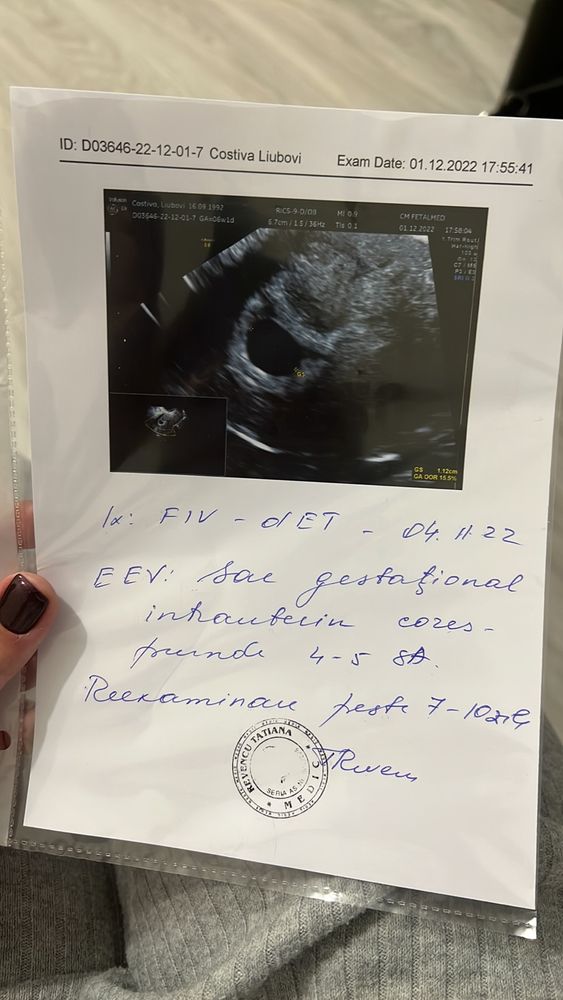

второе узи я сделала 1 декабря. Срок был 6 недель 2 дня.

на узи увеличенное плодное яйцо размер 1.12см эмбрион не визуализируется. ну думаю может рано. 2 декабря улетаю из Молдовы (там делала эко) и лечу в США.

Первое фото 6 недель и 2 дня. Второе и третье фото 7 недель.